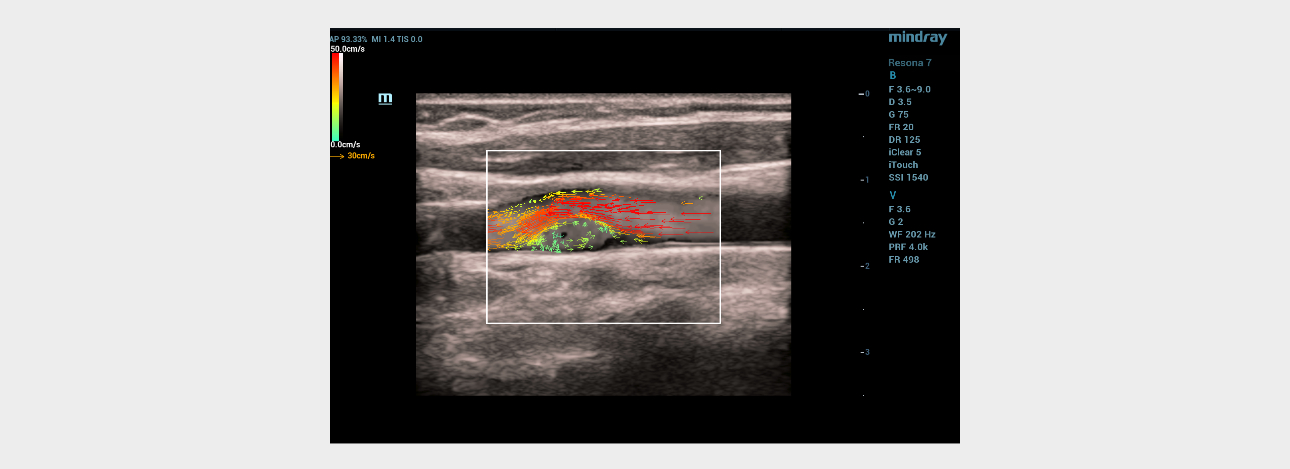

When the vector analysis mode (V Flow) was activated, the complete filling of the lumen of the left common carotid artery in the bifurcation area with colored vector arrows was clearly traced. The following changes were registered immediately after the linear hyperechoic structure: 1) shorter color arrows compared to arrows from the main blood flow in the vessel; 2) the arrows had a different color pattern (green, blue, yellow) in contrast to the red and orange arrows of the main stream; 3) the short arrows had a multidirectional, vortex-like direction in contrast to the laminar flow, which was determined over the pathological area of the vessel with a hyperechoic linear structure (Fig. 4). Given the absence of signs of flotation of hyperechoic linear formations and the topical symmetry of the location, it was assumed that these changes are characteristic of the carotid web.

aotid-web-v-flow-fig4-pc

Fig 4. Ultrasound of the carotid sinus using the V Flow mode.

Ultrasound vector analysis of blood flow

The V Flow mode made it possible to clearly see the full filling of the vessel lumen with colored arrows directly behind the hyperechoic linear formation on the left. The direction, color and size of the arrows in this area of interest clearly provided information about the slow-speed, retrograde and then vortex-like flow of blood in the vessel, which explained the poor color filling of the vessel lumen directly behind the hyperechoic linear structure in the color Doppler mapping mode, due to the high dependence of the latter on the speed and direction of moving blood particles (erythrocytes). The technology of vector analysis of blood flow made it possible to exclude the presence of an atherosclerotic plaque or a parietal thrombus.